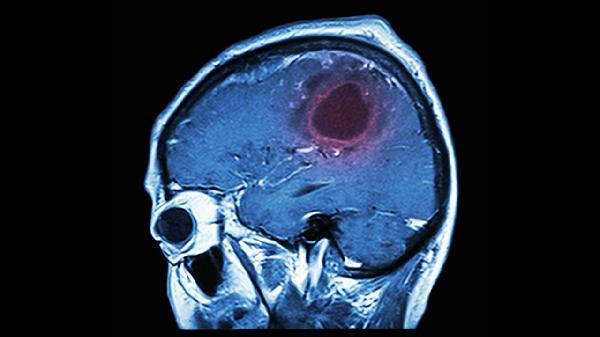

脑血栓导致腿没知觉还能怎么锻炼

当脑血栓导致腿部失去知觉时,可以借助被动关节活动、器械辅助训练、平衡练习、神经肌肉电刺激以及水中运动等方法来进行康复锻炼。下肢感觉障碍多与运动神经受损、血液循环不畅等因素相关,因此需要在专业康复医生的指导下,制定适合个人情况的康复计划。